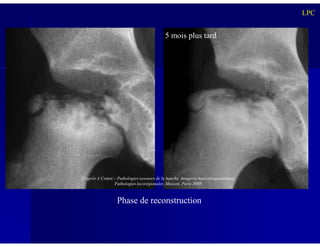

Stade de Reconstruction:

Reconstruction et remodelage de la tête fémorale

avec une densité osseuse redevenant

progressivement normale

5 mois plus tard

Phase de reconstruction

D’après A Cotten – Pathologies osseuses de la hanche. Imagerie musculosquelettique.

Pathologies locorégionales. Masson, Paris 2008.